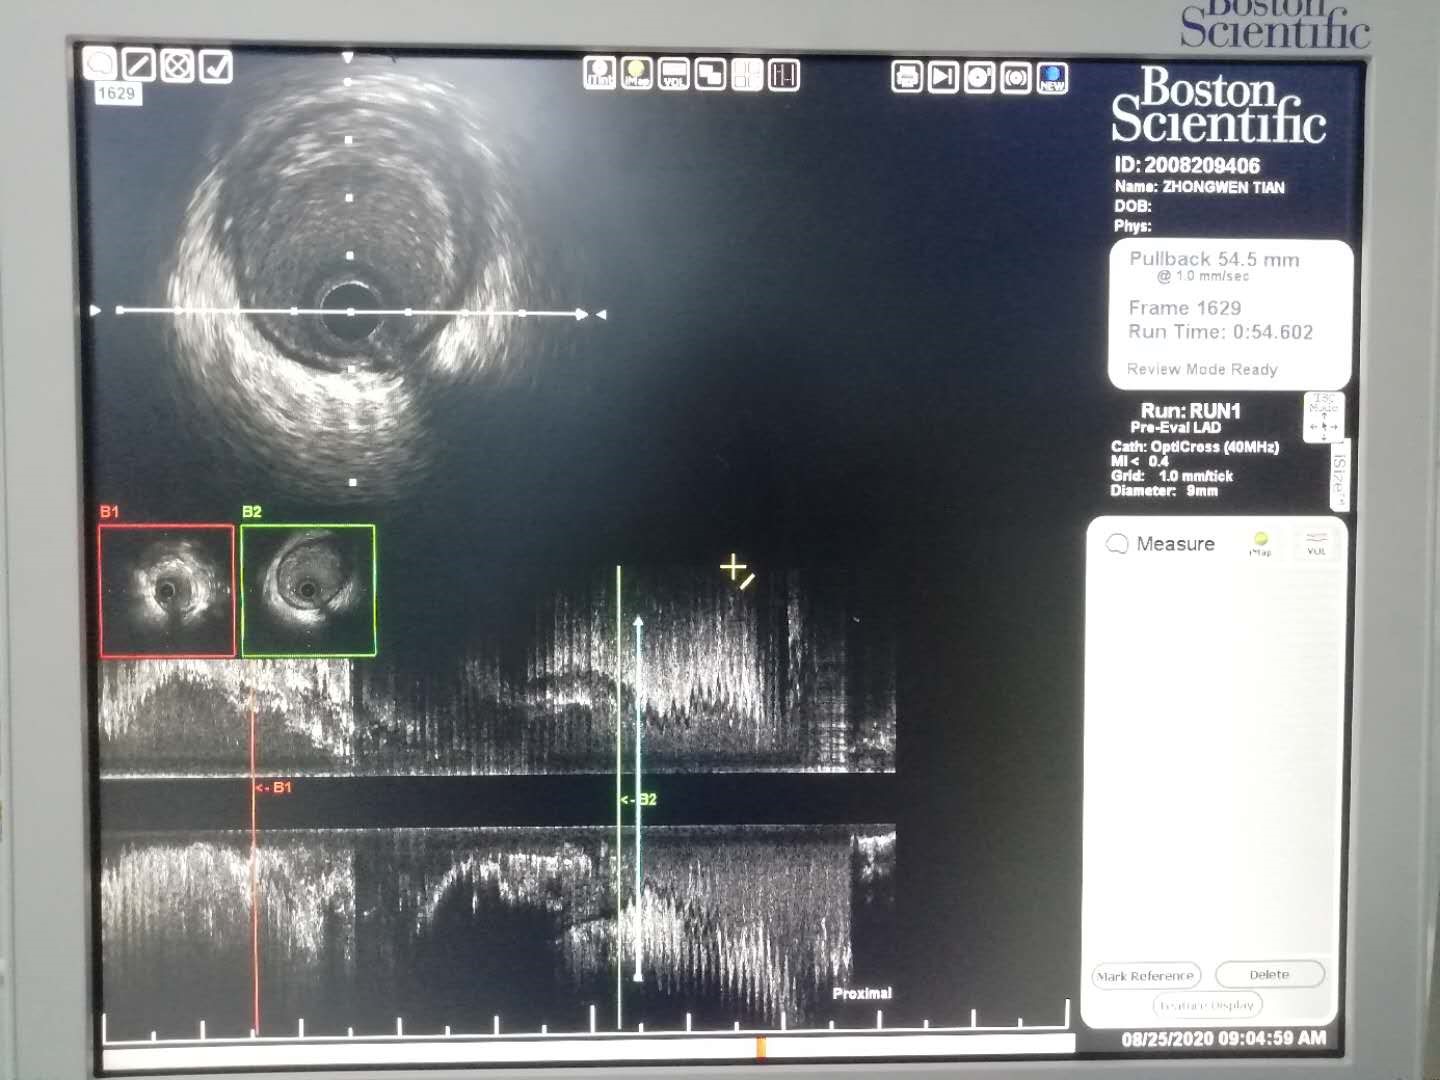

近日,心血管内三科成功实施我院首例冠状动脉血管内超声(IVUS)检查术,为冠心病精准介入治疗提供了“鹰眼”。此项手术实属通辽地区首例。

患者,72岁,男性,8年前曾因冠心病于外院行冠状动脉支架植入术,术后未规律用药,近期反复发作胸闷、胸痛入住我院心血管内三科寻求进一步治疗。经过术前科室治疗团队精心准备,于8月24日在局麻下行冠状动脉造影术,造影显示前降支原支架内再狭窄80%。据此结果下一步拟行支架内药物球囊扩张术。因既往外院介入资料缺失,相关药物球囊规格(尺寸及型号)常规方法很难精准测量。在征得患者及家属同意后首先使用血管内超声对前降支支架内外病变进行IVUS初步检测,其三维重建图像可用于进行斑块容积的定量测定,并根据与邻近结构如分支血管等的关系进行定位,从而对病变进展和消退的定量研究。最终根据IVUS检测结果提示的精准数据选择合适规格的药物球囊进行充分扩张及药物释放,再次IVUS检查评估治疗效果令人非常满意。目前,患者恢复良好,无胸闷、胸痛症状发作,活动耐力明显提升。

据心血管内三科杜建军主任介绍,冠状动脉血管内超声(IVUS)显像是将超声技术和心导管技术相结合,通过导管的方法将微型化的超声探头送入管腔内,可提供血管横截面的图像。依靠其准确的定性诊断和精确的定量测定,IVUS在冠状动脉疾病的诊断和指导治疗方面,发挥着非常重要的作用,尤其是在药物涂层支架(DES)时代,对进一步改善介入治疗的效果,降低再狭窄和防治并发症等方面均起着重要的指导作用。